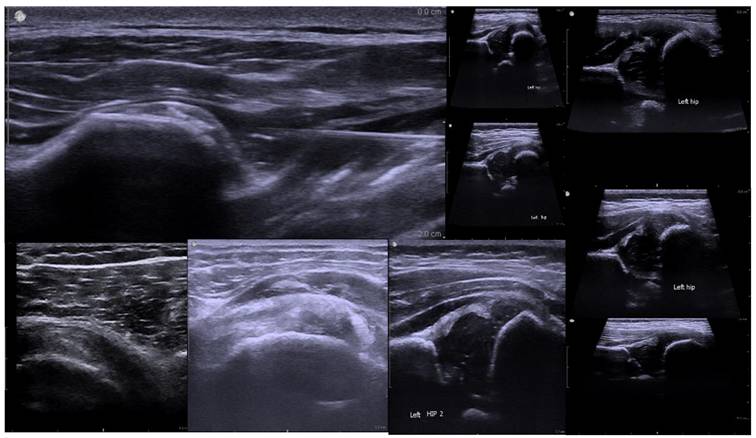

For the assessment of Developmental Dysplasia of the Hip (DDH), imaging primarily targeted key anatomical structures including the femoral head, acetabulum, and ilium. The Graf classification method, which evaluates hip joint stability through the measurement of the α and β angles, was adopted as the clinical reference standard. Figure 1 illustrates a representative hip joint ultrasound image, highlighting the femoral head's position within the acetabulum and labeling the femoral head, acetabulum, and ilium—structures essential for determining joint alignment and identifying abnormalities.

Figure 1

Ultrasound Image of the Hip Joint in Developmental Dysplasia of the Hip (DDH).